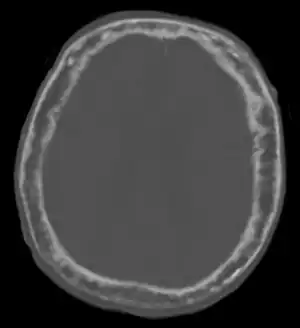

![]() | |

| "This 92 year-old male patient presented for assessment of sudden inability to move half his body. An incidental finding was marked thickening of the calvarium. The diploic space is widened and there are ill-defined sclerotic and lucent areas throughout. The cortex is thickened and irregular. The findings probably correspond to the 'cotton wool spots' seen on plain films in the later stages of Paget’s disease." | |